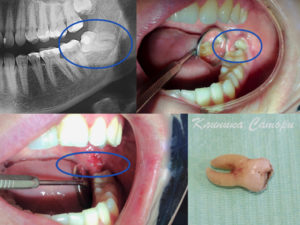

Воспаление капюшона возникает, когда зуб мудрости прорезывается через слизистую оболочку одним или несколькими буграми коронки. Т.е. получается ситуация, когда жевательная поверхность коронки зуба частично уже открыта, а оставшаяся часть – еще прикрыта слизистой оболочкой. Слизистая оболочка, нависающая над коронкой прорезывающегося зуба мудрости, называется Капюшоном (рис.1).

Под поверхностью капюшона создаются благоприятные условия для размножения микробов, которые и вызывают воспаление. Воспаление капюшона показано на рис.2-3. Это заболевание также имеет официальное название – Перикоронит. Если у Вас болит десна возле зуба мудрости, то скорее всего это связано именно с воспалением капюшона.

- Кариес зубов мудрости – симптомами могут быть боли на кислую, сладкую пищу, холодовые раздражители. Такие боли проходят сразу же после того, как раздражитель перестает действовать. Лечить или удалять такой зуб должен решать стоматолог. Это будет зависеть от правильности положения зуба, необходимости его для протезирования и т.д.Однако в некоторых случаях определить причину болей (а также причинный зуб) бывает достаточно сложно. Например, бывают ситуации, когда прорезывающийся зуб мудрости давит своей коронкой на впереди стоящий седьмой зуб, вызывая его разрушение (рис.7,9). В этом случае кариозный очаг располагается на дельней поверхности седьмого зуба около десны или даже чуть ниже нее.Диагностировать это можно, как правило, с помощью рентгена. На рис.7,9 Вы можете увидеть такой кариозный очаг, который выглядит как интенсивное затемнение (указано стрелками).